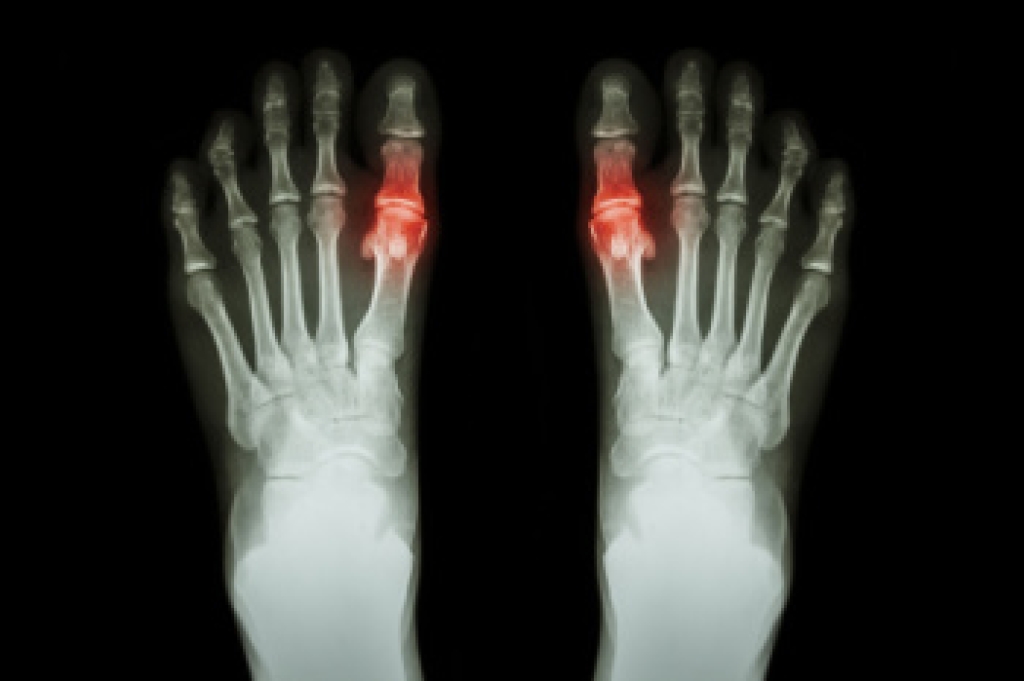

Gout is a form of arthritis caused by the buildup of uric acid crystals in the joints. It often affects the big toe, but can also impact other joints such as the knees, ankles, and wrists. A gout attack typically comes on suddenly, causing intense pain, swelling, and redness in the affected joint. These flare-ups may occur after consuming foods high in purines, such as red meat, seafood, and alcohol, which increase uric acid levels in the blood. Other risk factors include obesity, dehydration, and certain medications. To diagnose gout, a doctor may examine the affected joint, perform blood tests to check uric acid levels or take a sample of fluid from the joint to look for uric acid crystals under a microscope. If you are suffering from gout, it is suggested that you contact a podiatrist who can offer you effective relief and prevention methods.

Gout is a form of arthritis that is characterized by sudden, severe attacks of pain, redness, and tenderness in the joints. The condition usually affects the joint at the base of the big toe. A gout attack can occur at any random time, such as the middle of the night while you are asleep.

- Intense Joint Pain - Usually around the large joint of your big toe, and it most severe within the first four to twelve hours

- Inflammation and Redness -Affected joints may become swollen, tender, warm and red